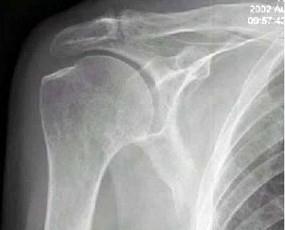

问题 右肩关节活动不便1年多,体检发现右手上抬不能,后展受限,行右肩关节摄片如图示,最好的诊断是 ( )

选项 A、右肩关节滑囊炎 B、以上都不是 C、右肱骨骨质疏松 D、右肩关节周围炎 E、正常右肩关节

答案 D